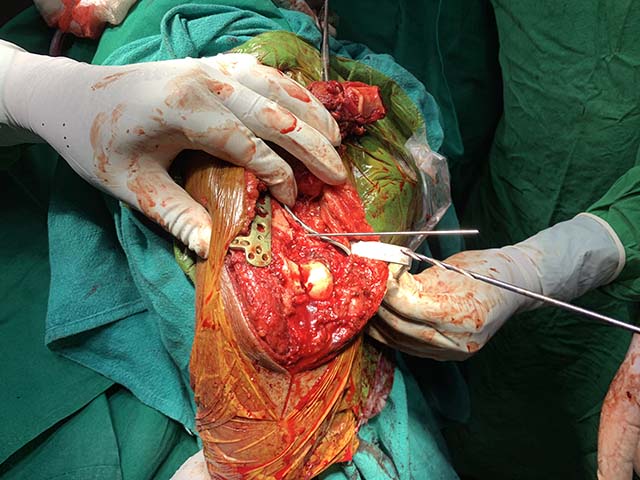

Complex Distal Humerus Comminuted Fracture

Complex Distal Humerus Comminuted Fracture

Complex Distal Humerus Comminuted Fracture

Complex Distal Humerus Comminuted Fracture

Complex Distal Humerus Comminuted Fracture

Complex Distal Humerus Comminuted Fracture

Complex Distal Humerus Comminuted Fracture

Complex Distal Humerus Comminuted Fracture

Complex Distal Humerus Comminuted Fracture

Complex Distal Humerus Comminuted Fracture

Complex Distal Humerus Comminuted Fracture

Complex Distal Humerus Comminuted Fracture

Complex Distal Humerus Comminuted Fracture

Complex Distal Humerus Comminuted Fracture